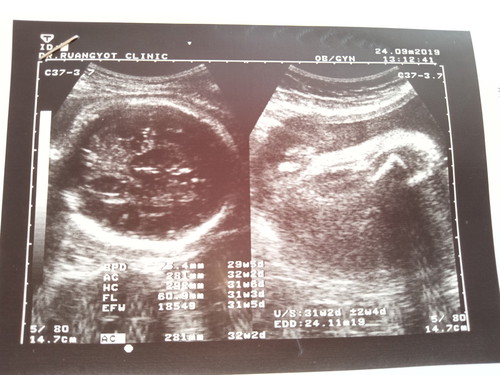

31+5วีคแล้วค่ะอยากถามแม่ๆที่รู้นะค่ะ

อยากรู้น้ำหนักลูกแต่ดูไม่เป็นอ่ะค่ะเขาดูกัน ตรงไหนแล้วน้ำหนักถึงเกณฑ์ป่าวค่ะ ขอบคุณสำหรับคำตอบแม่ๆนะค่ะ

1854g ค่ะ